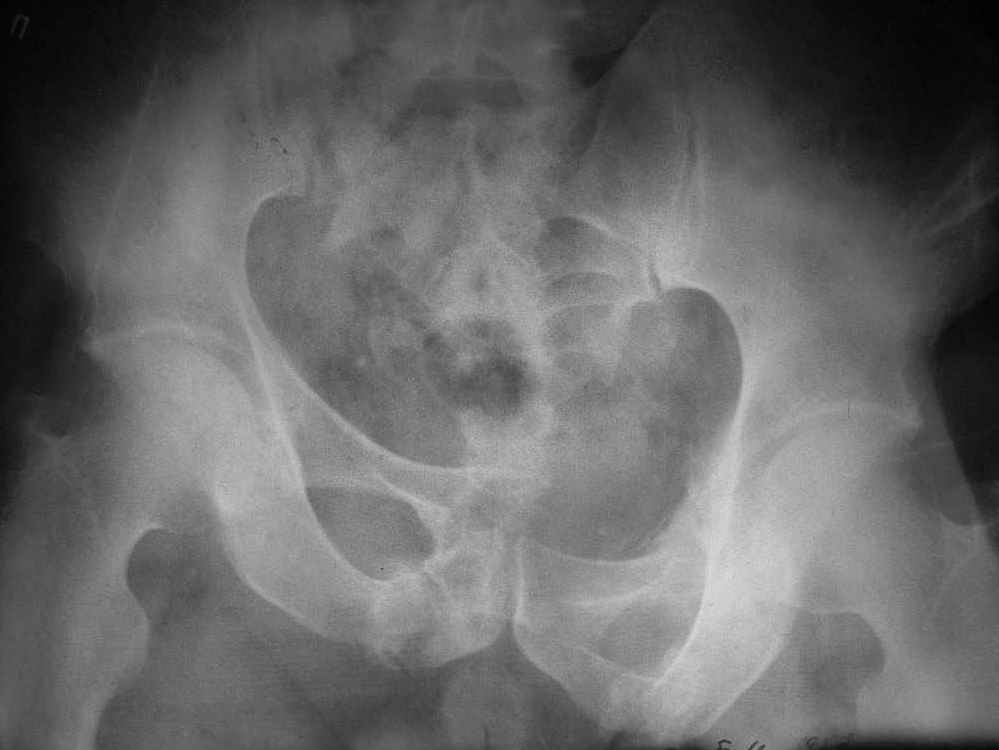

Исходная картина